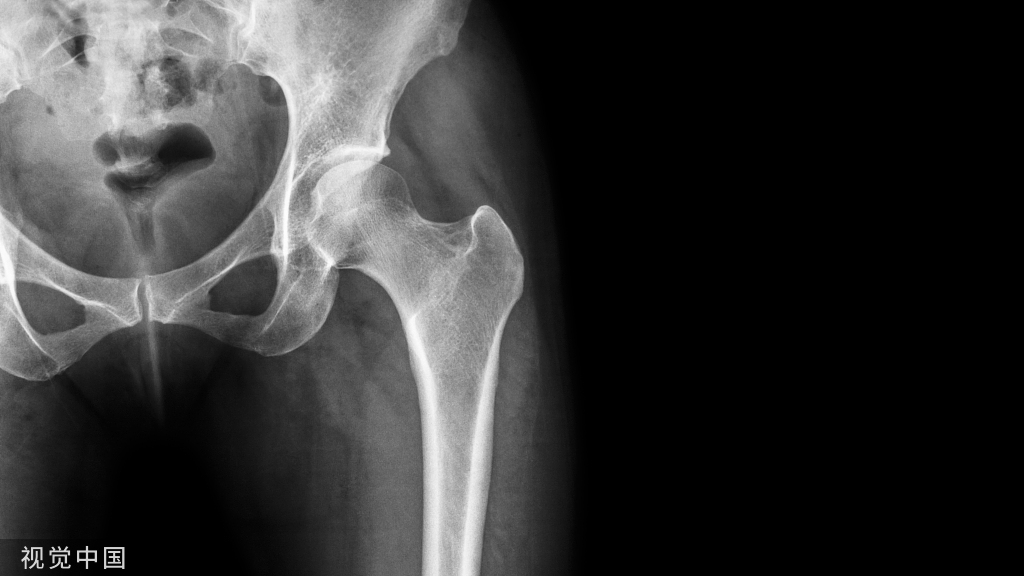

1.半髋关节置换

2.全髋关节置换

3.股骨粗隆间骨折